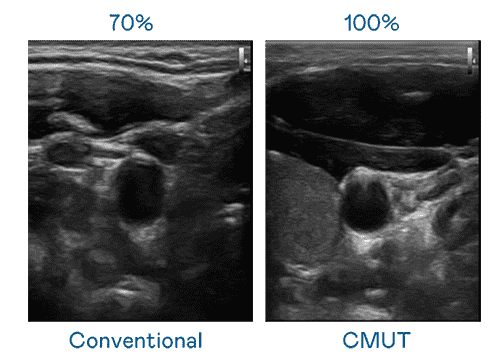

CMUT 技术是一种用电容式微机电元件来产生超音波讯号的技术。。。。与传统 PZT 压电式技术相比,,CMUT 频宽增加 30%,,,更宽频的超音波讯号让影像解析度大幅提升,,,是实现高影像品质医疗超音波扫描、、、、促进精准医疗发展的关键技术。。

大频宽带来超清晰影像

超音波影像的解析度高低,,,,首先取决于探头能发出的讯号频宽。。彩神vll CMUT 可提供高清晰的超音波讯号,,提供高频宽、、、高灵敏度、、、影像纹理细节更高的超音波影像,,协助医护人员缩短影像判读时间及利用精准的医疗影像进行诊断。。。